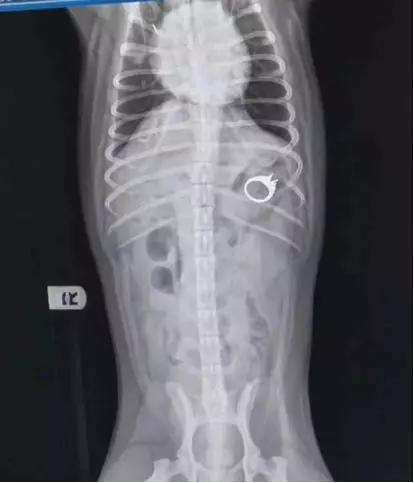

Shelby赶紧把Patrick送到兽医院,拍了X光,戒指果然在Patrick肚子中。

医生警告,这颗戒指已经超过可以自然排泄出来的尺寸,如果不赶快动手术拿出来,锋利的钻戒边缘可能会让Patrick有生命危险。